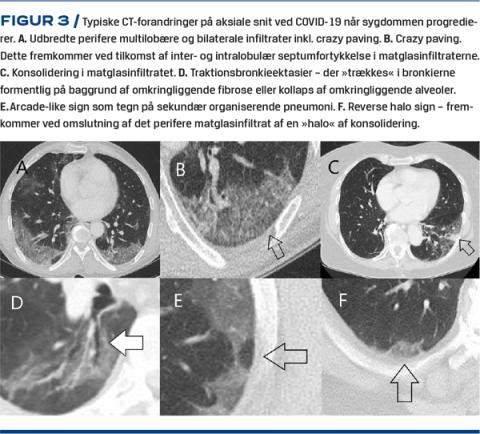

Karakteristika for COVID-19 ved konventionel røntgen undersøgelse af thorax

Studier på området er sparsomme, og forandringerne er primært beskrevet kasuistisk. Konventionel røntgenundersøgelse af thorax er uspecifik, har lav sensitivitet for COVID-19 [6] og anbefales ikke til direkte diagnostik af COVID-19, om end undersøgelsen er indiceret til differentialdiagnostik eller behandlingsmonitorering af patienter med COVID-19. I milde tilfælde kan røntgenbilledet være normalt eller med så diskrete matglasforandringer, at de enten ikke kan ses på røntgen eller ses som helt diffuse »slør«. I typiske tilfælde ses afrundede bilaterale og perifert beliggende vattede infiltrater (Figur 1A), men i mere fremskredne tilfælde kan røntgenbilledet vise mere udtalte diffuse og konsoliderede infiltrater, som kan udvikle sig til et ARDS-lignende billede (Figur 1C) [7]. Vores erfaring er, at man i flere stadier af sygdommen ser peribronkial cuffing og/eller interstitiel (retikulær) tegning, oftest med normal hjertestørrelse og altså uden mistanke om stase. Som beskrevet ved CT af thorax (se nedenfor) er pleural ansamling et sjældent fund.